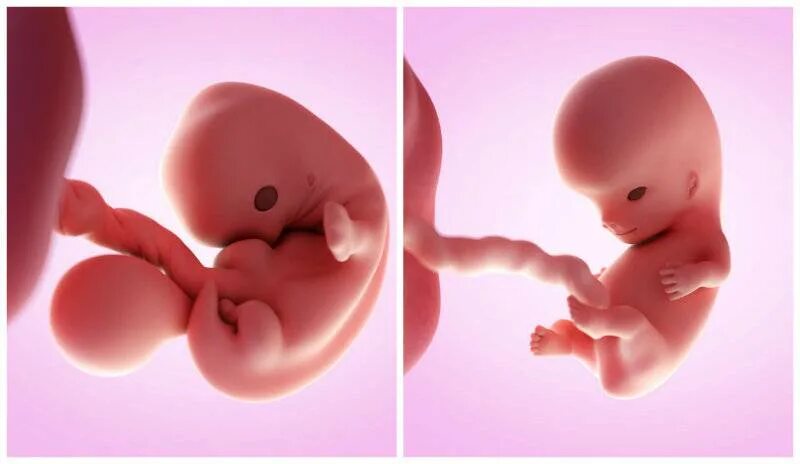

Плод 10 см